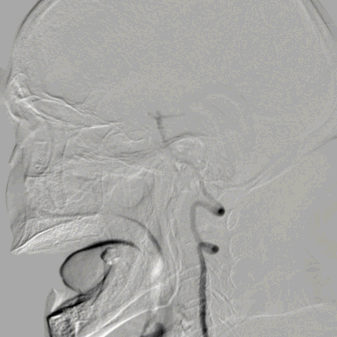

RVA超选造影仍可见后循环丰富的软膜支向右侧颞叶代偿供血。

FlowGate 2同轴Catalyst 7、Synchro 2多次调整后穿过C1起始闭塞处,MicroPort Pioneer 2.5mm×20mm球囊C1起始处缓慢扩张,顺球囊Catalyst 7穿过闭塞段,继续向前推进FlowGate 2失败, Catalyst 7 C1抽吸出长条血栓。

Catalyst 7 C1抽吸出大负荷血栓。

Catalyst 7再次通过闭塞处于C2-C4近端抽吸,再无血栓抽出,球囊辅助通过(BTA)技术无法将CAT7带入C4远端,CAT减容任务完成,使用Solitaire FR 6×30支架行完整BADDASS技术, 6×30支架前行张力非常大,释放时并无法顺利推出Rebar 18微导管,导致支架释放略近于预期位置。

支架释放位置不理想,而且前行过程中导致血栓前移,支架并未覆盖血栓头端,经验告诉我们,仅靠软膜支的独立系统可能会通过BGC的血流阻断弥补前向压力(P),远端未覆盖血栓可能会因为血栓之间的粘附力而一并拖出。

充盈FlowGate 2,CAT 7施加张力,希望CAT 7能在支架回撤过程中抓住血栓尾端,但CAT 7在虹吸弯纹丝不动,负压下同时撤出支架与DAC。

BADDASS技术下支架取出长条血栓,3D-DSA可见眼动脉下方重度狭窄,CAT 7在张力下的上行切割狭窄处,导致小夹层产生。

术后RICA造影 :mTICI 3级。